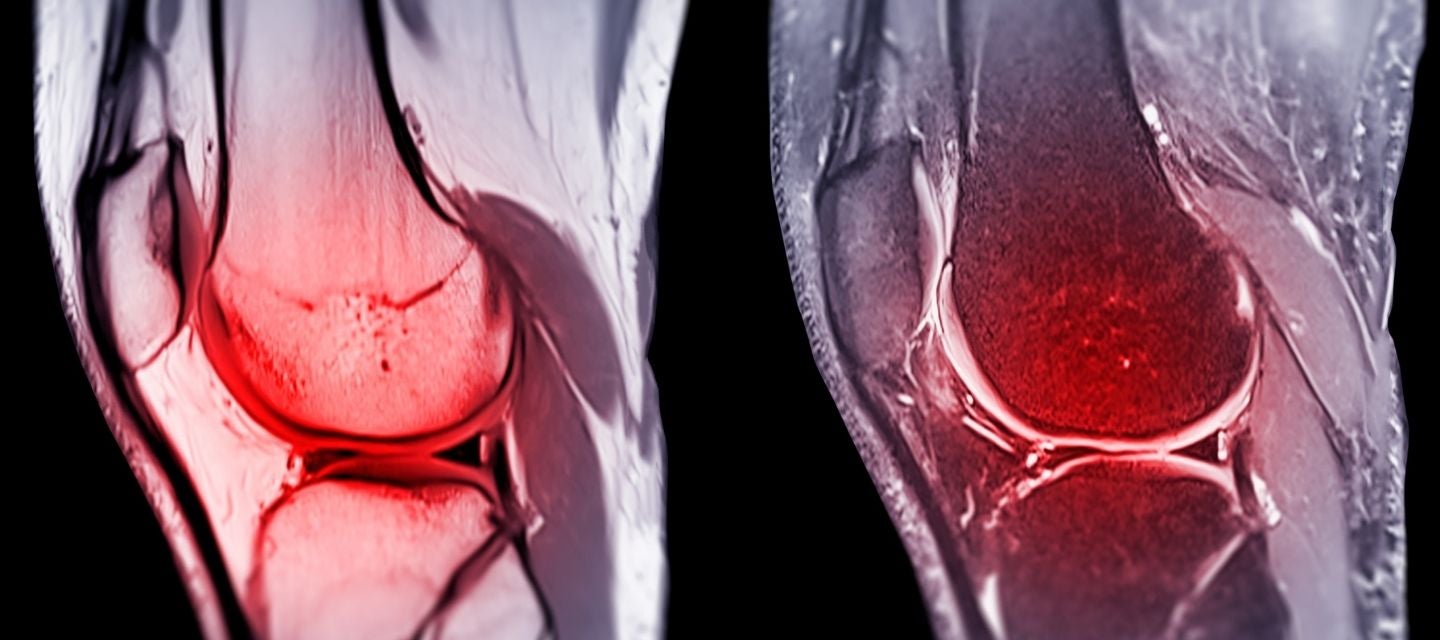

Knee Arthritis, MRI Stock Image C027/1212 Science Photo Library Radiology Assistant Mri Knee Anatomy basic knee mri checklist. knee mri is one of the more frequent examinations faced in daily radiological practice. this article is based on a presentation by david rubin and adapted for the radiology assistant by robin smithuis. magnetic resonance imaging (mri) of the knee is a common diagnostic examination that is performed for the. Anatomy arthrogram. Radiology Assistant Mri Knee.